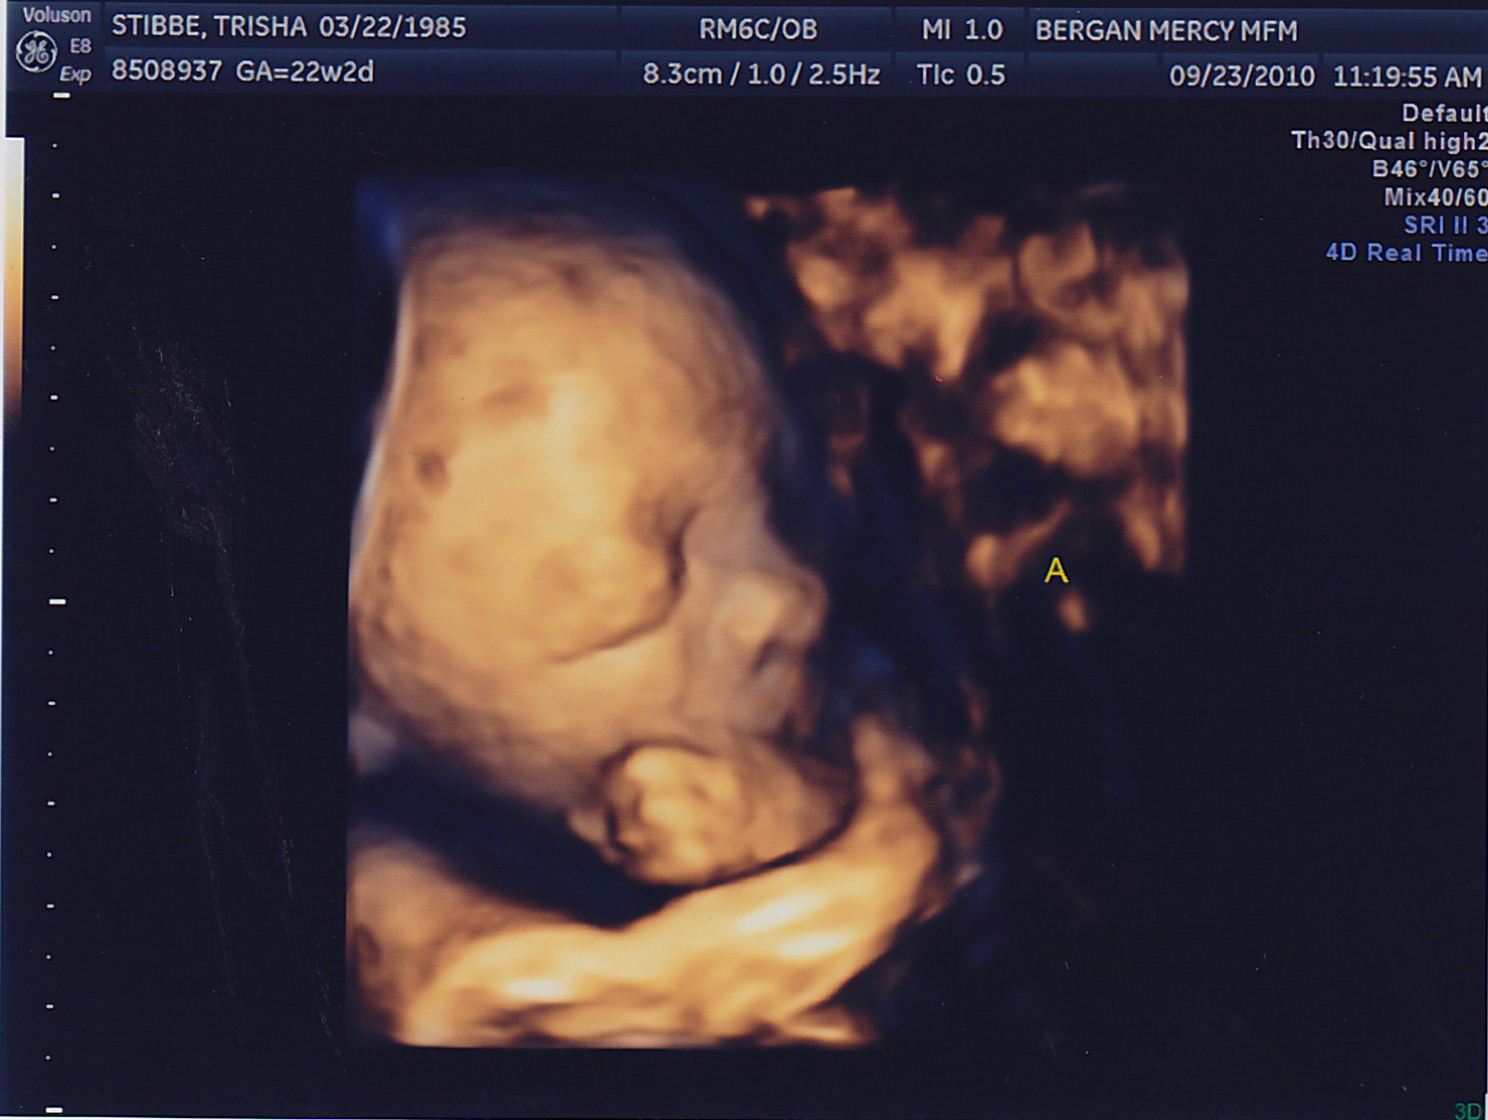

My sonographer Briana surprised me with 4D pictures! She was only able to get a good image of Baby A because Baby B is facing my back. One funny thing–for a while now they have both been on my right side and I could swear I looked lopsided. Then it started to kind of even out a little, and its because Baby A moved to the left! They’re finally learning to share 🙂 Last week they were both head down, and this week they’re both head up. Squirmy little guys.

Here are the little guys most recent pictures!

Hi Trish and Adam. Great pictures, I love the 4D’s. It’s amazing! It looks like Baby A is smiling in the one picture. He must be thinking about his Grandma. 🙂 Little B was being camera shy though. Little bugger.